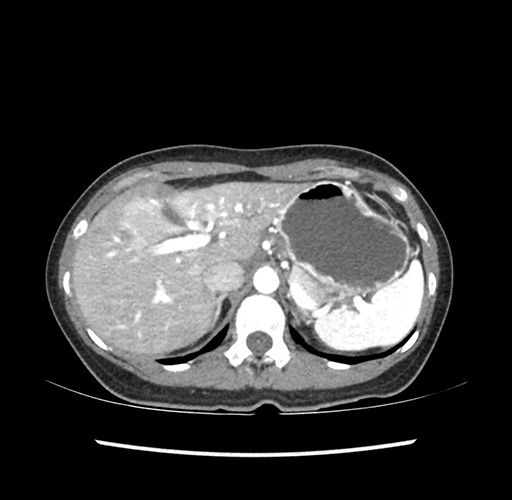

Imaging Analysis

Look through the patient's CT scan to identify any areas of concern for the necessary procedure.

Based on your CT findings, which issue(s) would give reason for "planned slowing down moment(s)" in this case?

Considering a standard left lateral sectionectomy procedure, what step(s) of the operation would you do differently in this case ?